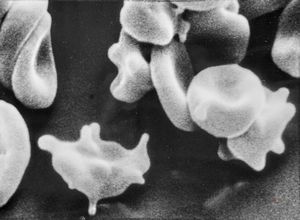

blood - trombocytes

thrombocyte